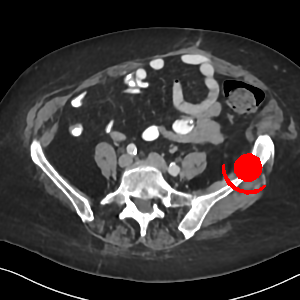

Visual comparison. As shown in Fig. 5, metallic implants such as spinal rods and hip prosthesis cause severe streaky artifacts and metal shadows, which obscure bone structures around them. cGan-CT cannot recover image intensity correctly for both cases. Sinogram domain or dual-domain methods perform much better than cGan-CT. LI, NMAR, and CNNMAR introduce strong secondary artifacts and distort the whole images. In NMAR images, there are fake bone structures around the metals, which is related to segmentation error in the prior image from strong metal artifacts. The segmentation error is also visible in NMAR sinogram. CNNMAR cannot restore the correct bone structures between rods in case 1. The tissues around the metals are over-smoothed in DuDoNet because LI sinogram and image are used as inputs, and the missing information cannot be inferred later. Our model retains more structural information than DuDoNet and generates anatomically more faithful artifact-reduced images.

Visual comparison. Fig. 7 shows two clinical CT images with metal artifacts. Case 1 is with moderate metal artifacts. cGan-CT does not suppress the artifacts completely and generates some fake details. LI, NMAR, CNN-MAR remove all the artifacts but introduce new streak artifacts, which is caused by the discontinuity in the corrected sinogram. DuDoNet outputs over-smoothed sinogram, which leads to blurred tissues close to the metal implants, such as muscle and bone. Only our model can provide realistic enhanced sinogram and remove the artifacts while retaining the structure of nearby tissues. Case 2 is very challenging as the rods bring strong metal shadows and bright artifacts around the vertebra. cGan-CT recovers the shape of vertebra but changes the overall image intensity. Other sinogram inpainting methods fail as the soft tissue and bone near the rods are heavily distorted. Our model removes part of the dark bands and reproduces correct anatomical structures around the rods.